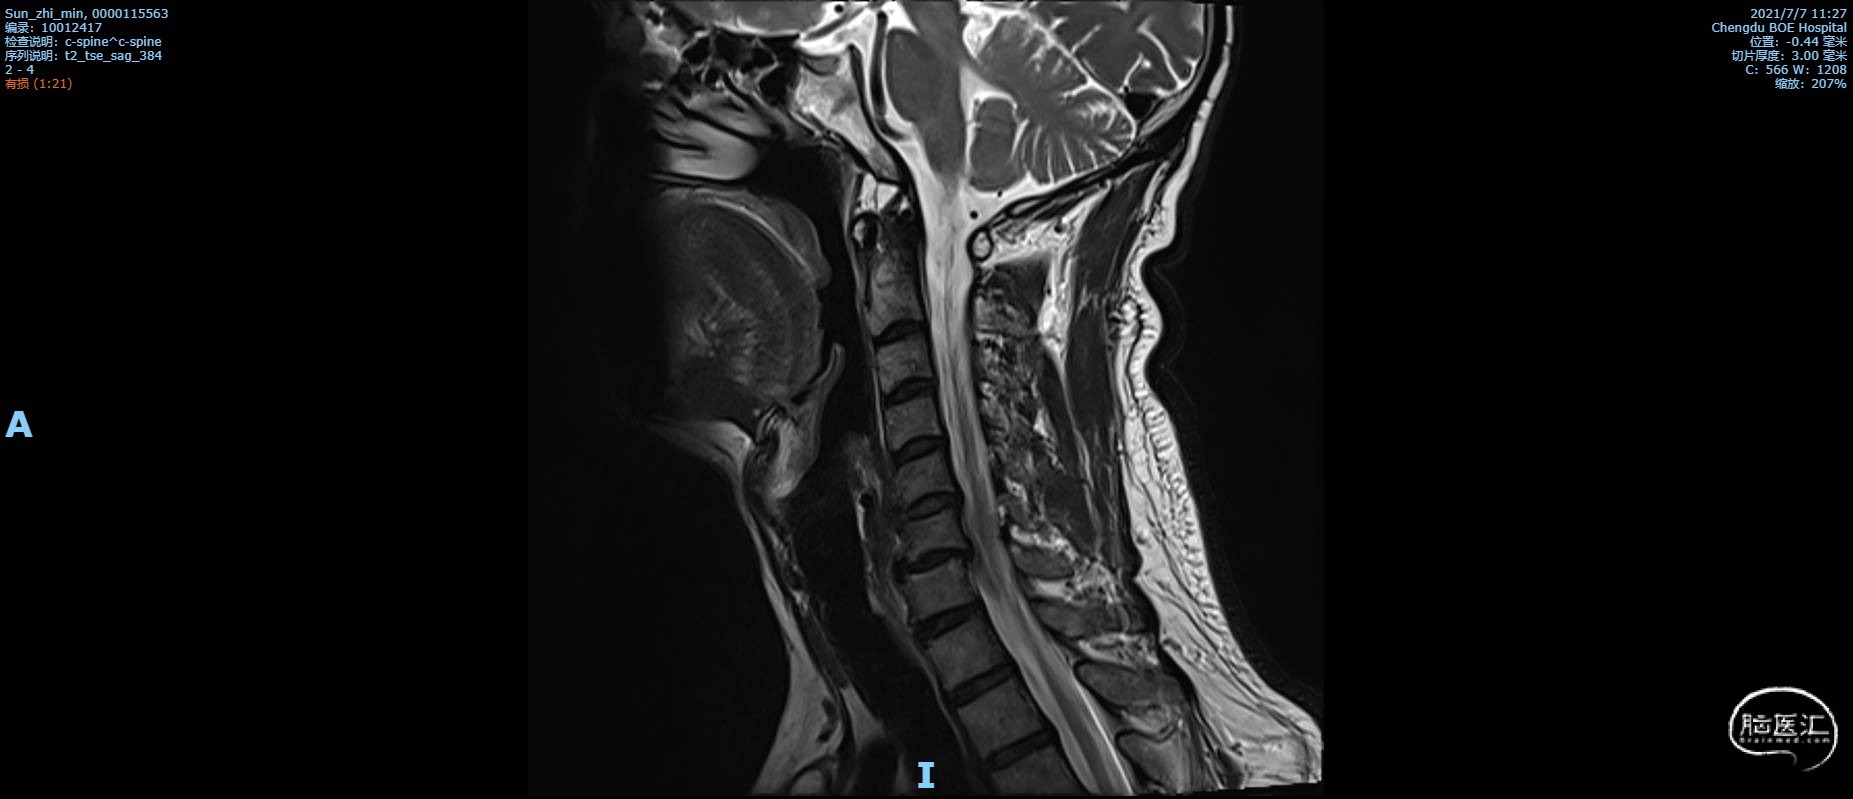

术前复查MRI矢状位颈椎MRI T2 加权像,C6椎体不稳定,C6/C7椎间盘脱出,局部脊髓受压,斑片状信号改变,颈椎管狭窄。

颈椎MRI T2 加权像1

颈椎MRI T2 加权像2

颈椎MRI T2 加权像3